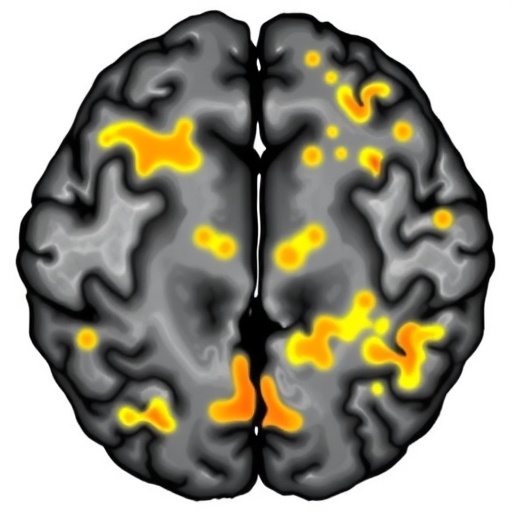

The researchers analyzed large-scale longitudinal MRI data spanning multiple years from a diverse cohort of aging individuals. Employing cutting-edge segmentation algorithms, they precisely delineated WMH regions at successive time intervals. Crucially, they did not just quantify overall lesion volume but mapped changes across distinct white matter tracts and cerebral regions. This allowed the team to detect specific patterns in how WMHs emerged, expanded, and interacted with surrounding brain tissue over time. These spatiotemporal trajectories revealed that WMHs do not grow in a uniform or random manner; rather, they follow regionally distinct patterns that may reflect underlying pathophysiological mechanisms unique to various brain areas.

A central finding of the study is that the progression of WMHs exhibits distinct phases that vary across brain regions. Early in the disease course, certain periventricular regions—adjacent to the brain’s fluid-filled ventricles—showed rapid lesion expansion, whereas deep white matter areas exhibited more gradual changes. Intriguingly, posterior regions of the brain had markedly different progression timelines compared to frontal regions, suggesting a region-specific vulnerability or differing disease drivers. The study’s fine-scaled temporal resolution illuminated these differences, which could not be appreciated with single-timepoint imaging snapshots.